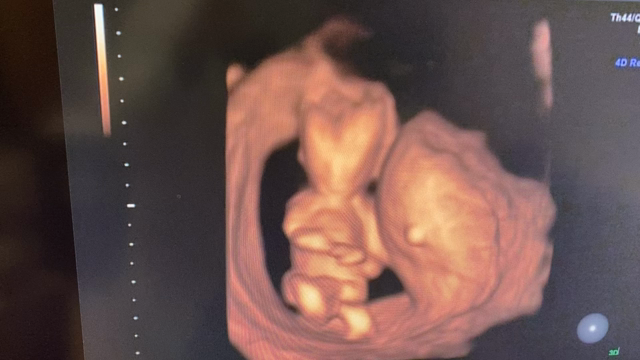

✳︎12w5d 頸部浮腫のこと✳︎

2020年12月6日